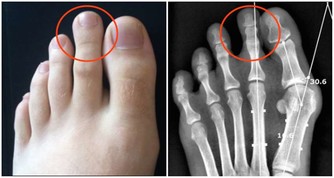

8、膝蓋左右腳的腳後跟外側部分和膝蓋是有直接關連的,

如果你是膝蓋酸痛或慢性膝關節疼痛的患者,可以試著按摩這個區域來減緩疼痛。